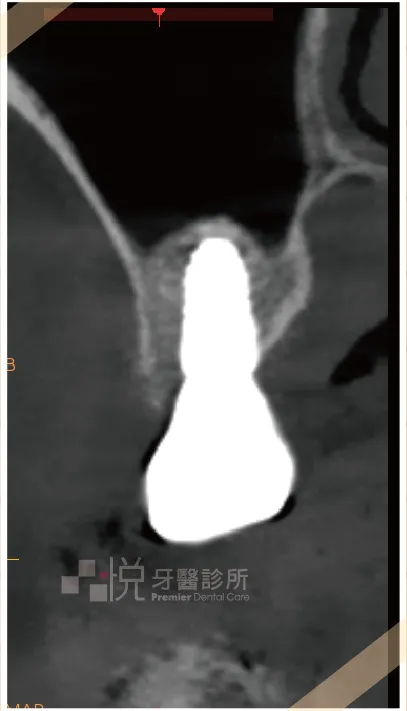

「上顎後牙區」是最常遇到鼻竇相關問題的區域。如上圖,可以發現上顎後牙區無論有沒有牙齒,常會遇到患者鼻竇空間過大,導致剩餘骨頭高度不足的情況。

一般為了達到理想咬合功能及植牙的長久穩定,在臨床上盡可能希望使用常規長度植牙植體(長度約為 8 mm 到 10 mm ),但因鼻竇的因素,時常面臨剩餘骨頭高度不足於植入正常長度之植體。

治療如果忽略剩餘骨高度,直接把植體貫穿鼻竇的空間時,我們身體可能會把植體視為外來物,會有引發鼻竇發炎的風險。

為了避免植體直接刺破鼻竇的空間,在植牙時常會執行「鼻竇增高術」,確保植體周圍有足夠的骨頭包圍並避免植體直接穿進鼻竇裡。